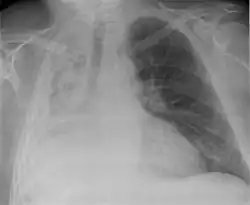

Atelectasis is the partial collapse or closure of a lung resulting in reduced or absence in gas exchange. It is usually unilateral, affecting part or all of one lung.[2] It is a condition where the alveoli are deflated down to little or no volume, as distinct from pulmonary consolidation, in which they are filled with liquid. It is often referred to informally as a collapsed lung, although more accurately it usually involves only a partial collapse, and that ambiguous term is also informally used for a fully collapsed lung caused by a pneumothorax.[1]

It is a very common finding in chest X-rays and other radiological studies, and may be caused by normal exhalation or by various medical conditions. Although frequently described as a collapse of lung tissue, atelectasis is not synonymous with a pneumothorax, which is a more specific condition that can cause atelectasis. Acute atelectasis may occur as a post-operative complication or as a result of surfactant deficiency. In premature babies, this leads to infant respiratory distress syndrome.

Clinically significant atelectasis is generally visible on chest X-ray; findings can include lung opacification and/or loss of lung volume. Post-surgical atelectasis will be bibasal in pattern. Chest CT or bronchoscopy may be necessary if the cause of atelectasis is not clinically apparent. Direct signs of atelectasis include displacement of interlobar fissures and mobile structures within the thorax, overinflation of the unaffected ipsilateral lobe or contralateral lung, and opacification of the collapsed lobe. In addition to clinically significant findings on chest X-rays, patients may present with indirect signs and symptoms such as elevation of the diaphragm, shifting of the trachea, heart and mediastinum; displacement of the hilus and shifting granulomas.[13]